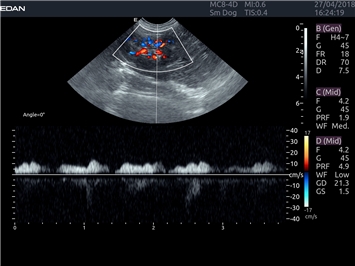

Трехмерная реконструкция ЦДК:

Да

Энергетический допплер:

Цветовой допплер:

Импульсно-волновой допплер:

Триплексное сканирование:

Дуплексное сканирование: